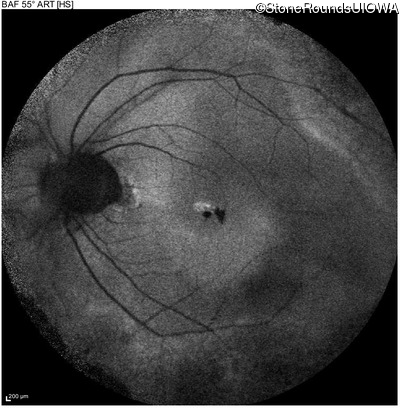

Blue Autofluorescence - Right - 20/25

Exemplar